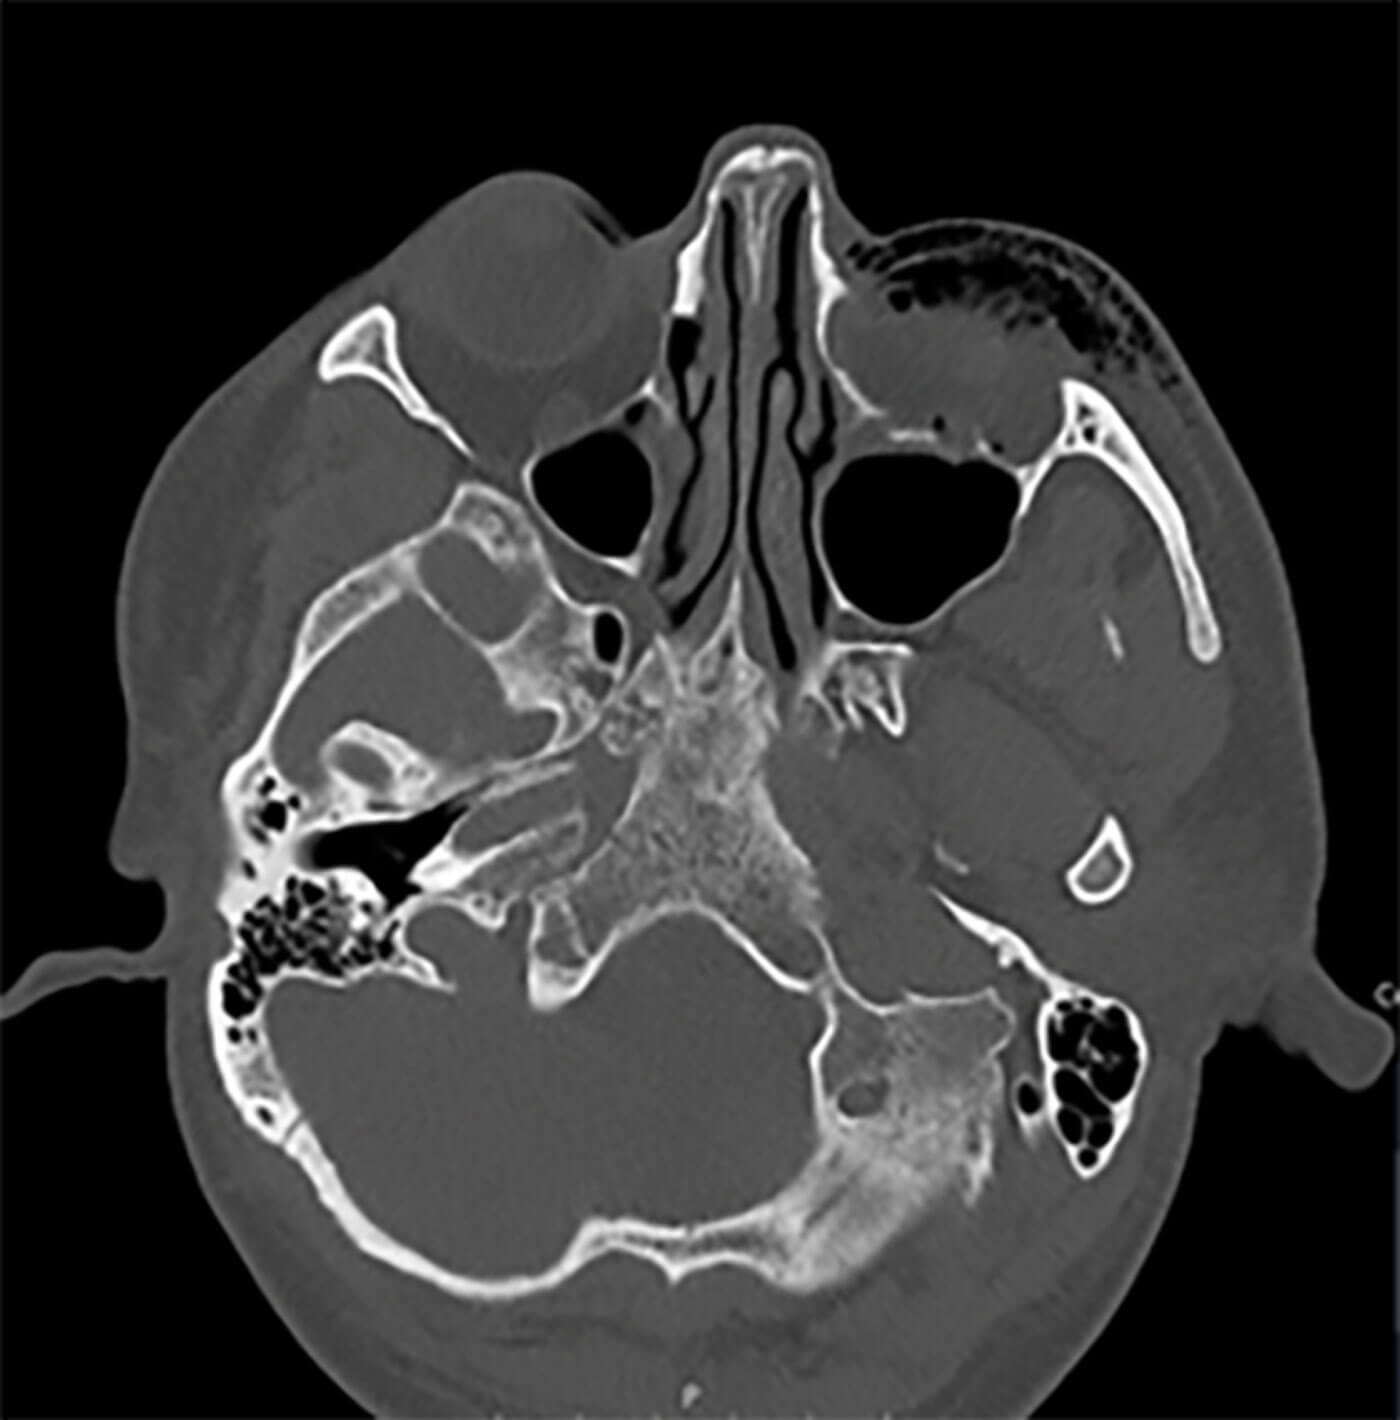

Figure 2: CT orbit demonstrating surgical emphysema in the left orbit.

There is comminuted fracture of the floor of the posterior left orbit and superior maxillary wall.

A computed tomographic (CT) orbits showed surgical emphysema and air in the subcutaneous soft tissues to the left orbit. There was also pneumocephalus in the postseptal fat around the optic nerve. There was a comminuted fracture of the floor of the posterior left orbit and superior maxillary wall (Figure 2). The patient was managed conservatively by his local maxillofacial team, but was subsequently lost to follow-up two months after presentation.